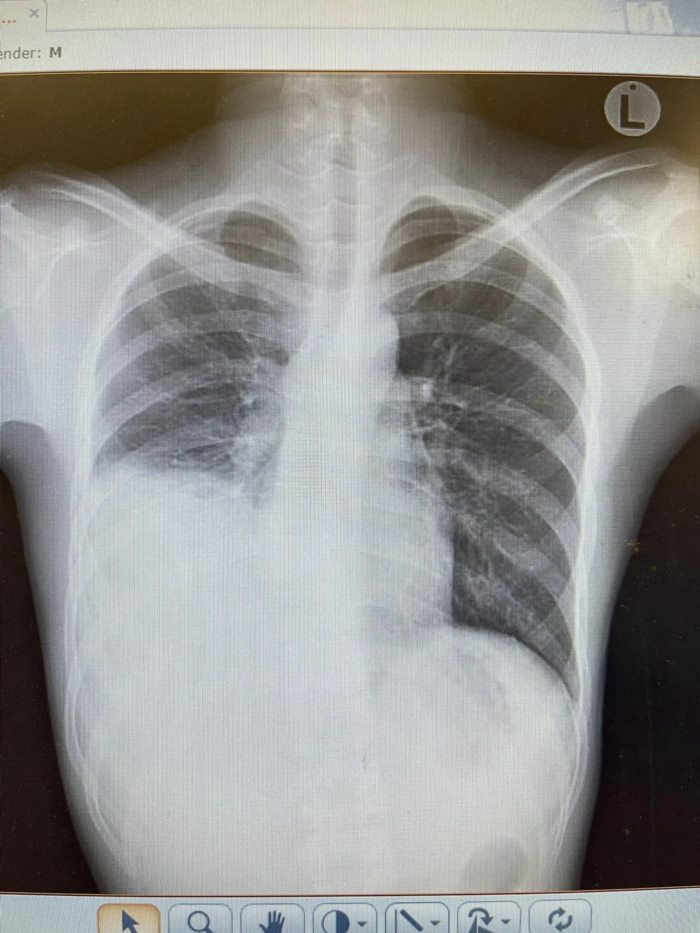

จากนั้นคนไข้ได้มาที่โรงพยาบาล นพ.สุรพันธ์ จึงมีการเอกซเรย์ปอดดู จนพบว่ามีโพรงฝีหนองในปอดขวาประมาณ 10 เซนติเมตร หมอรู้สึกแปลก ๆ เพราะโรคฝีในปอด (Lung abscess) ส่วนใหญ่มักจะเจอแบคทีเรียมากมาย แต่คนไข้รายนี้อายุยังน้อย แข็งแรงดี ไม่มีโรคประจำตัว แถมปอดยังไม่เหมือนอาการที่เกิดจากบุหรี่ไฟฟ้าอีกด้วย ซึ่งการดื่มเหล้าอาจจะทำให้ปอดอักเสบจากสารระคาย แต่ไม่น่าจะมีฝีในตับที่เกิดจากการติดเชื้อแบคทีเรีย